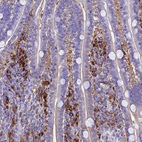

Immunohistochemistry analysis in human lung and skeletal muscle tissues using HPA041602 antibody. Corresponding FTL RNA-seq data are presented for the same tissues.